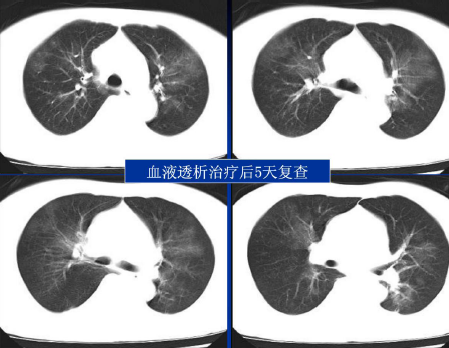

不同类型肺水肿的CT表现(上)

不同类型肺水肿的CT表现(下)